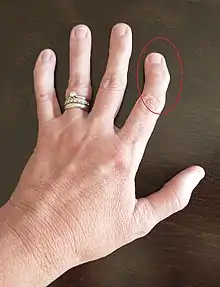

| A hand affected by rheumatoid arthritis, an autoimmune form of arthritis | |